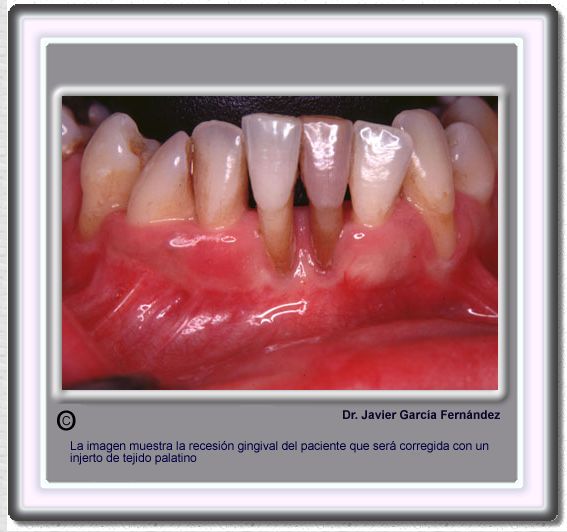

image 717